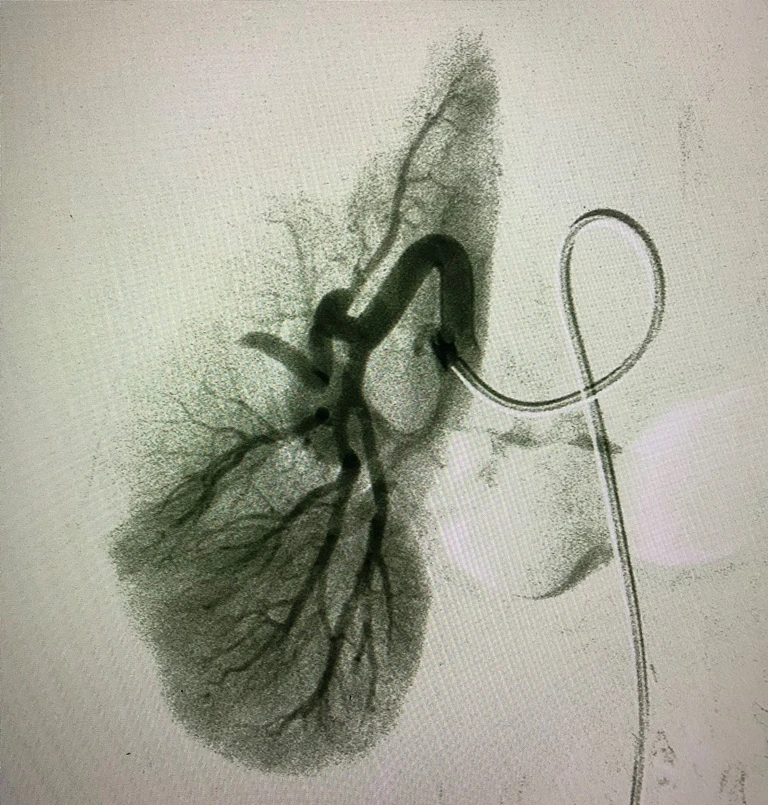

Kết quả xét nghiệm, chụp CT cho thấy bướu mỡ cơ mạch thận của bà rất to (87x121x100 mm) và đang chảy máu. Bệnh nhân được chỉ định can thiệp nội mạch cầm máu cấp cứu. Phương pháp này cho phép các bác sĩ khống chế tình trạng chảy máu và ngăn chặn hiệu quả nguồn máu nuôi bướu. Bà H. xuất viện chỉ 24 giờ sau với chức năng thận bình thường. Sau ba tháng, khối bướu dần tiêu nhỏ (giảm 25% thể tích) vì không còn nhận được máu nuôi, trong khi phần thận còn lại được bảo tồn.

Hình thận được bảo tồn sau thuyên tắc. Ảnh: HL